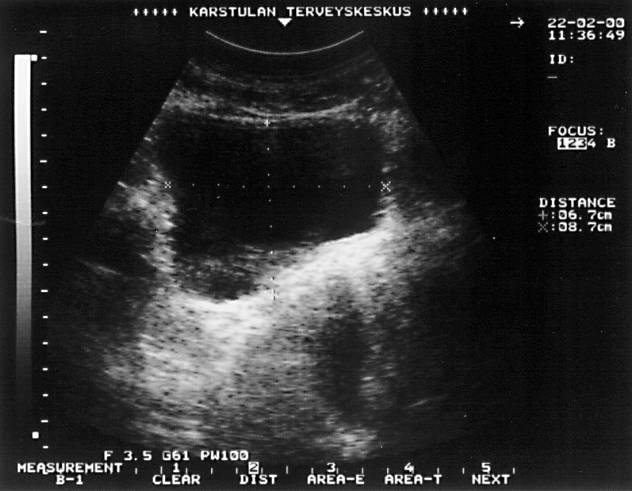

Urinary retention (transverse ultrasonographic picture). Urinary retention in an elderly man. The height of the urinary bladder measures 6.7 cm in a transverse ultrasonographic picture, the width measures 8.7 cm, and the length (in a longitudinal picture) measures 10.4 cm. The estimated minimum recidual urine volume is 0.6 × 10.4 × 6.7 × 8.7 = 364 ml.

Picture: Ilkka Kunnamo